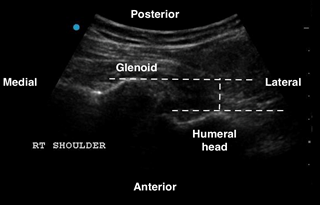

An anterior shoulder dislocation will show the humeral head displaced to the far field region of the screen, while the posterior dislocation will show the humeral head displaced to the near field region (Figures 3 and 4). A shoulder subluxation will show the humeral head partially sliding (or “dislocating”) in and out of the GHJ with shoulder movement (Figure 5). While less accurate, POCUS can also help identify fractures, such as the Hill-Sachs, the Bankart, or a humeral head fracture (Figure 6).

Secko MA, et al. has estimated a 100% sensitivity and specificity in diagnosing a shoulder dislocation by using the posterior approach technique. They also established that an anterior dislocation has a glenohumeral distance cutoff value of at least 0.5 cm.6

Figure 2: Right shoulder anterior dislocation